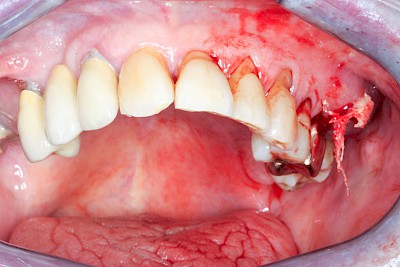

Schwellung mit Eiter: Abszess

Schwellungen im Zusammenhang mit akuten Entzündungen im Bereich der Zähne oder dem Zahnhalteapparat entstehen meist aufgrund schneller und starker Vermehrung von Bakterien sowie einer starken Abwehrreaktion des Körpers (Abszess). Diese Schwellungen entstehen meist in sehr kurzer Zeit – innerhalb von Stunden oder wenigen Tagen. Die Schwellungen sind sehr schmerzhaft. Nah am Zahnfleisch kann sich bei leichtem Druck auf die Schwellung Eiter entleeren. Mitunter fühlen sich die Menschen krank. In fortgeschrittenem Stadium kann auch Fieber auftreten. Hier ist sofort der Zahnarzt zu kontaktieren, um eine weitere Ausbreitung der Entzündung zu verhindern.